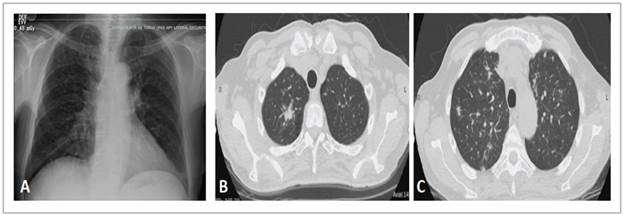

MODERATOR: a chest x-ray and tomography were taken, which are shown in Figure 1.

The chest x-ray shows interstitial opacities and mediastinal widening (Figure 1A); in immunocompromised patients, x-rays do not have good specificity or sensitivity for detecting respiratory diseases and differentiating among them. The chest HRCT shows random or diffuse micronodules (Figure 1C), although the centrilobular ones are most evident, associated with solid nodules, especially a spiculated one in the right upper lobe (Figure 1B). Micronodules with this distribution suggest hematogenous dissemination and generate a differential diagnosis of miliary tuberculosis, histoplasmosis and other fungal infections like candidiasis and disseminated blastomycosis; hematogenous metastasis of extrapulmonary tumors is also included, especially thy roid, melanoma, breast and kidney tumors 10.

On the other hand, nodules like the ones seen in the im ages are suggestive of tuberculosis and fungal infections, especially cryptococcosis; when they are surrounded by ground glass opacities, one of the differential diagnoses is Kaposi sarcoma.